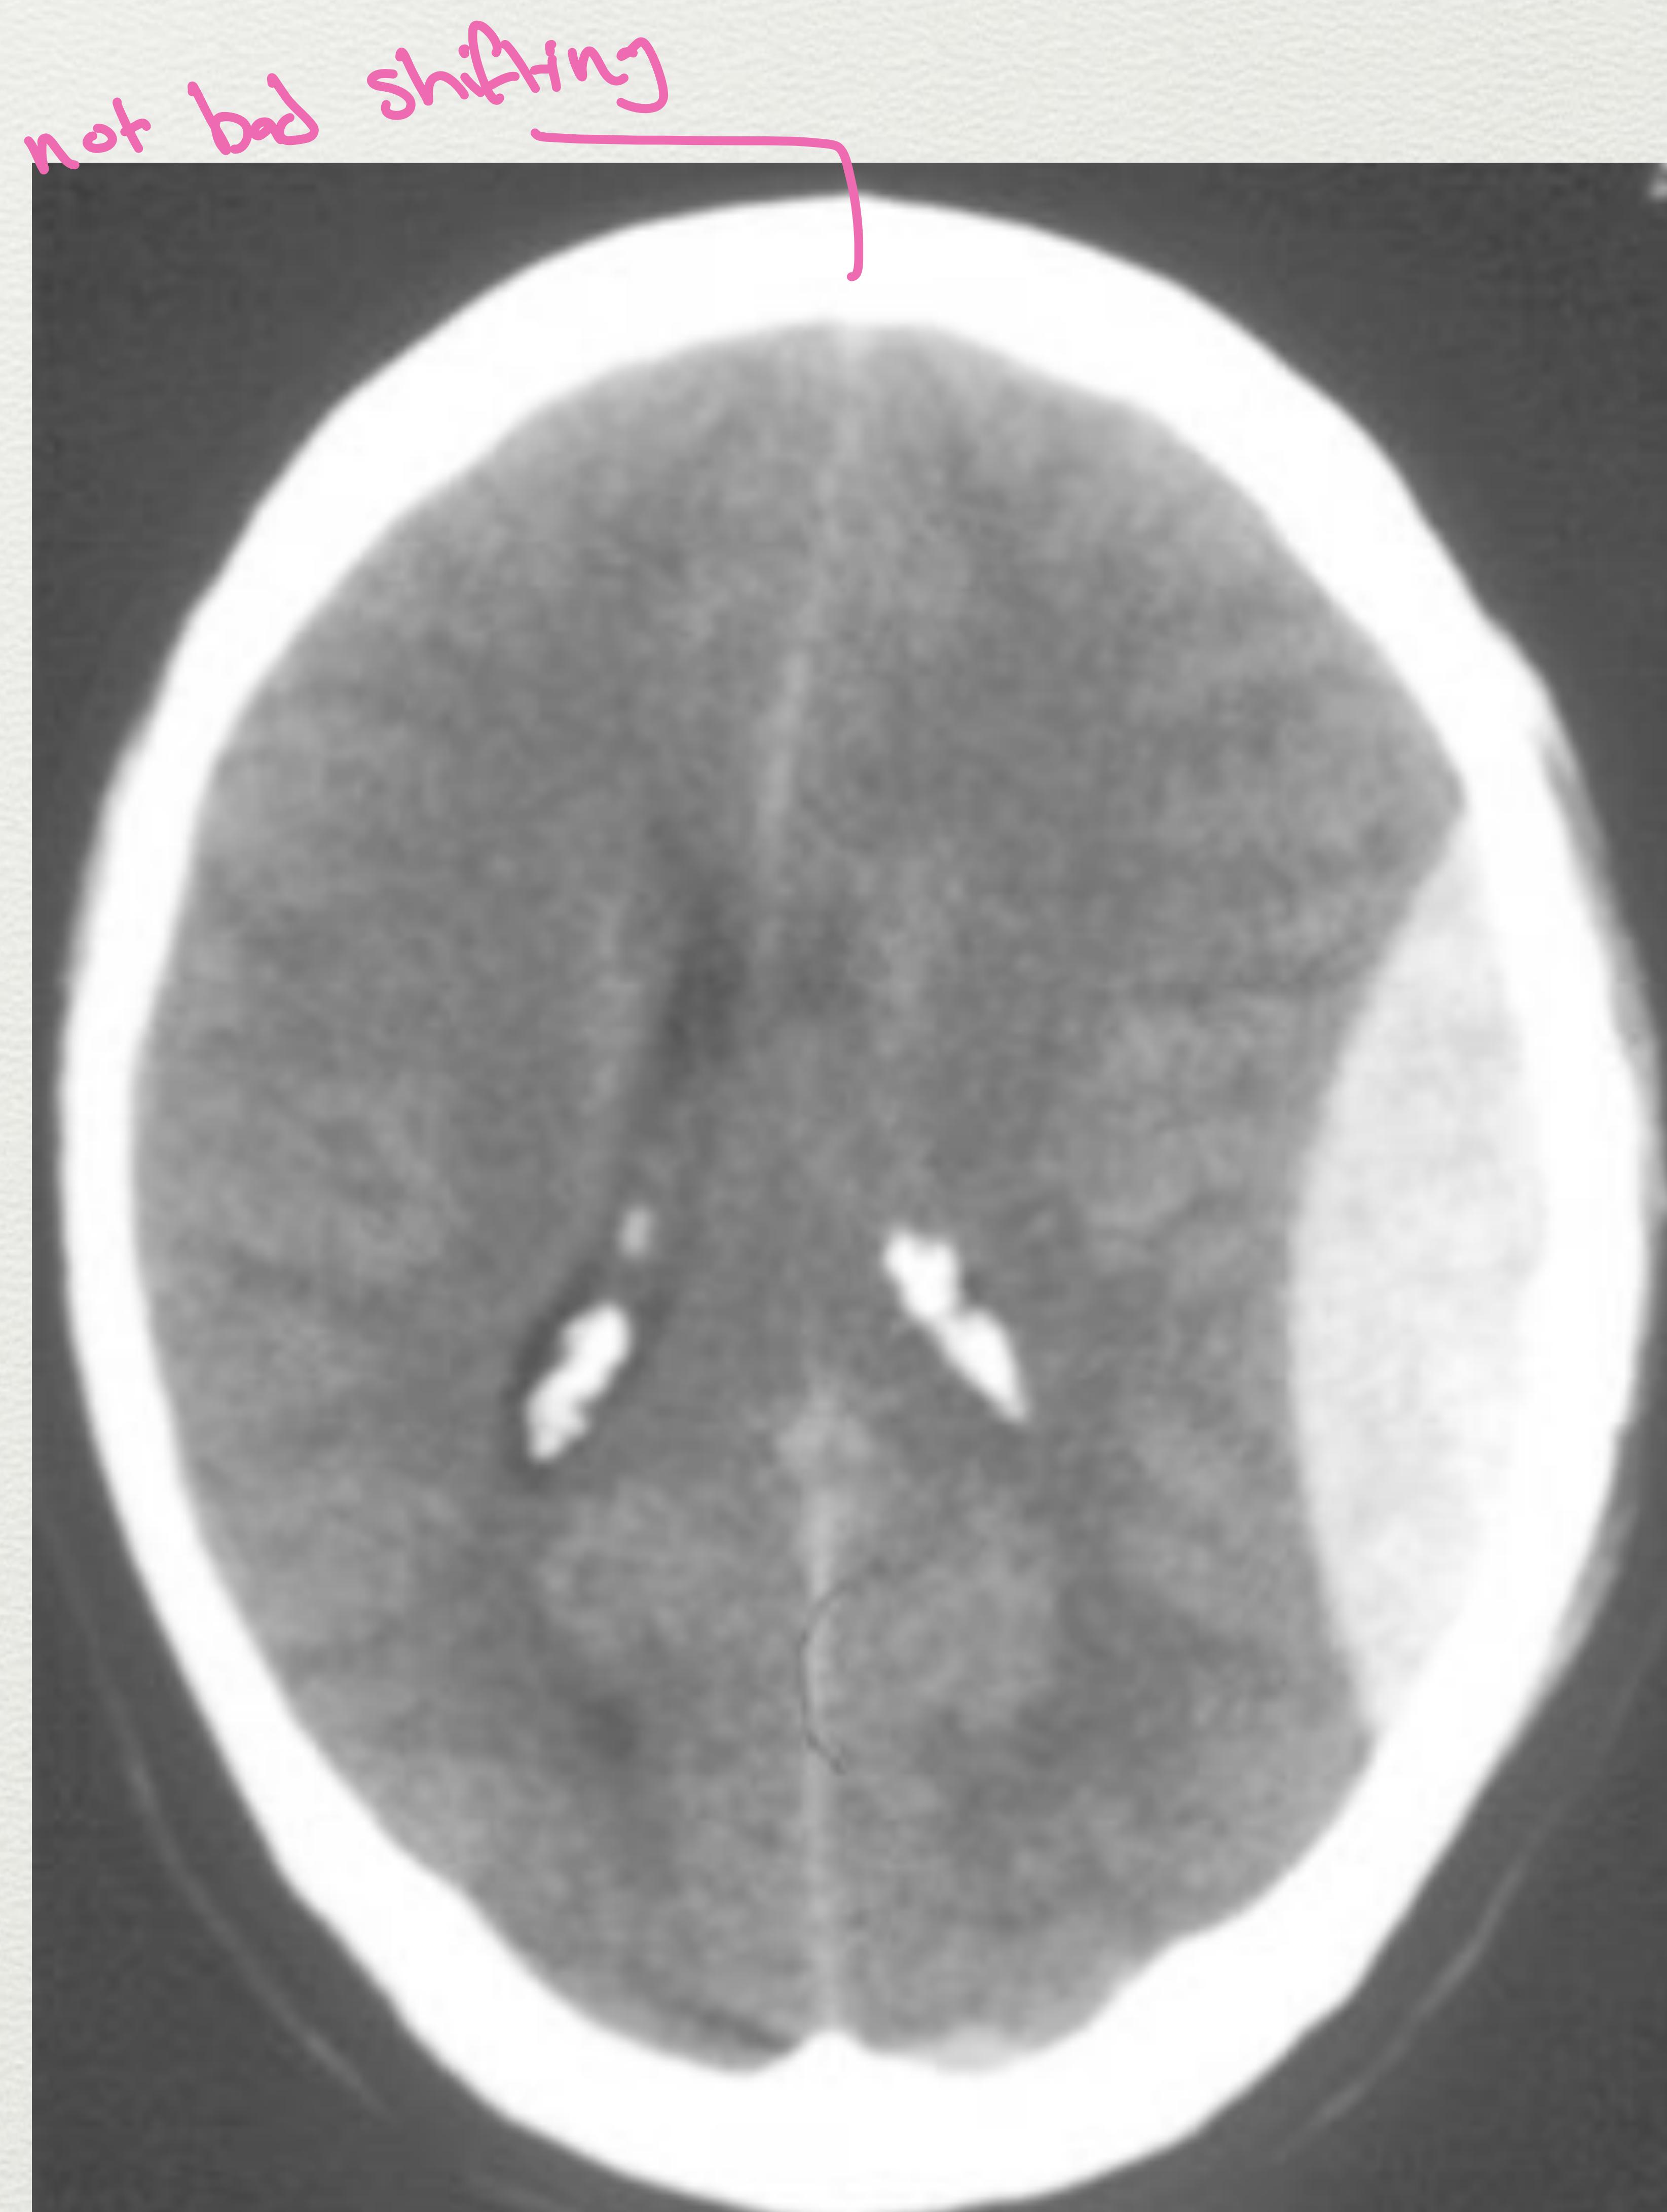

Epidural Hematoma (EDH)

- Usually from Middle Meningeal Artery tear with associated skull fracture.

- Most are temporal or parietal, but can occur in frontal and occipital lobes (rare in posterior fossa).

- Common in young adults.

- Appearance: Classic lenticular shape.

- Clinical Feature: Lucid Interval (Behaves totally normal then sudden deterioration/arrest).

- Risk: Brain herniation from Foramen magnum due to high pressure.

Axial CT scan showing a large, hyperdense, biconvex (lenticular) epidural hematoma.